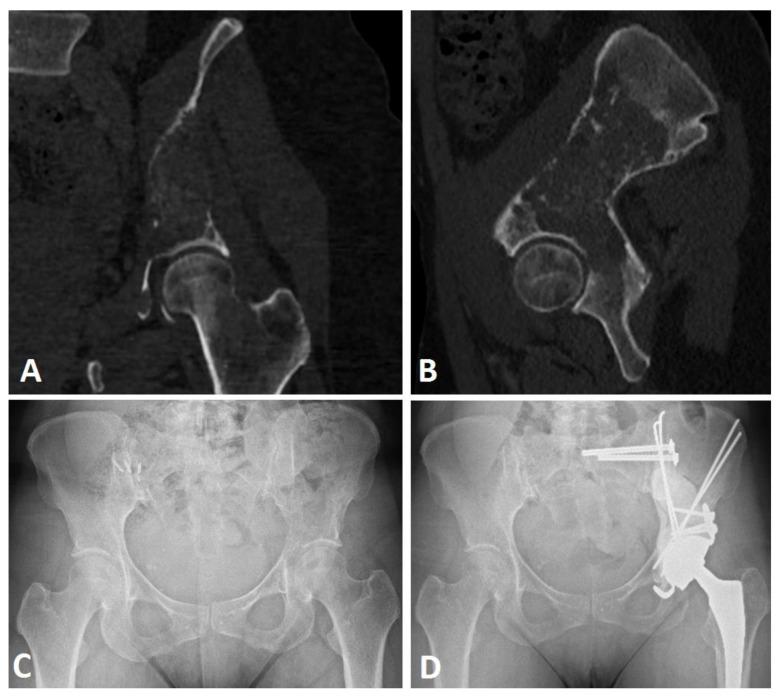

The Harrington surgical technique makes it possible to manage complex, extensive bone lesions using pins and cement to consolidate bone for acetabular cup positioning. However, it may be associated with a high reoperation rate, and the functional results of this surgery are not precisely described in the literature.

In a monocentric retrospective study including all patients operated on using the Harrington procedure associated with THA between 2005 and 2020, we aimed to assess preoperative and postoperative function, reoperation-free survival, and overall survival.

Functional improvement was significant for Parker scores (preoperative: 3.6 ± 2.0; 6-month follow-up: 6.6 ± 3.2; 12-month follow-up: 7.6 ± 2.1) and Musculoskeletal Tumor Society (MSTS) scores (preoperative: 31.1 ± 16.2%; 6-month follow-up: 67.7 ± 30.6%; 12-month follow-up: 82.4 ± 24.0%). Of the 21 patients included, the reoperation-free survival rate was 76.1% [CI 95%: 58.1-99.7] at six and twelve months, with the main complications being pin migration (50.0%) and infection (25%). The patient overall survival rate was 76.2% [95% CI: 59.9-96.7] at six months and 61.9% [95% CI: 59.9-96.7] at 12 months.

哈林顿手术技术通过使用钢针和骨水泥固定骨块来强化髋臼杯的位置,从而实现对复杂、广泛骨病变的处理。然而,该技术可能与较高的再次手术率相关,且其手术功能结果在文献中并未得到准确描述。

本单中心回顾性研究纳入了 2005 年至 2020 年间接受哈林顿手术联合全髋关节置换术的所有患者,旨在评估术前和术后功能、无再次手术生存率和总体生存率。

帕克评分(术前:3.6 ± 2.0;术后 6 个月:6.6 ± 3.2;术后 12 个月:7.6 ± 2.1)和肌肉骨骼肿瘤学会(MSTS)评分(术前:31.1 ± 16.2%;术后 6 个月:67.7 ± 30.6%;术后 12 个月:82.4 ± 24.0%)均有显著改善。21 例患者中,6 个月和 12 个月时无再次手术生存率分别为 76.1%(95%CI:58.1-99.7),主要并发症为钢针迁移(50.0%)和感染(25.0%)。患者总体生存率在 6 个月时为 76.2%(95%CI:59.9-96.7),12 个月时为 61.9%(95%CI:59.9-96.7)。